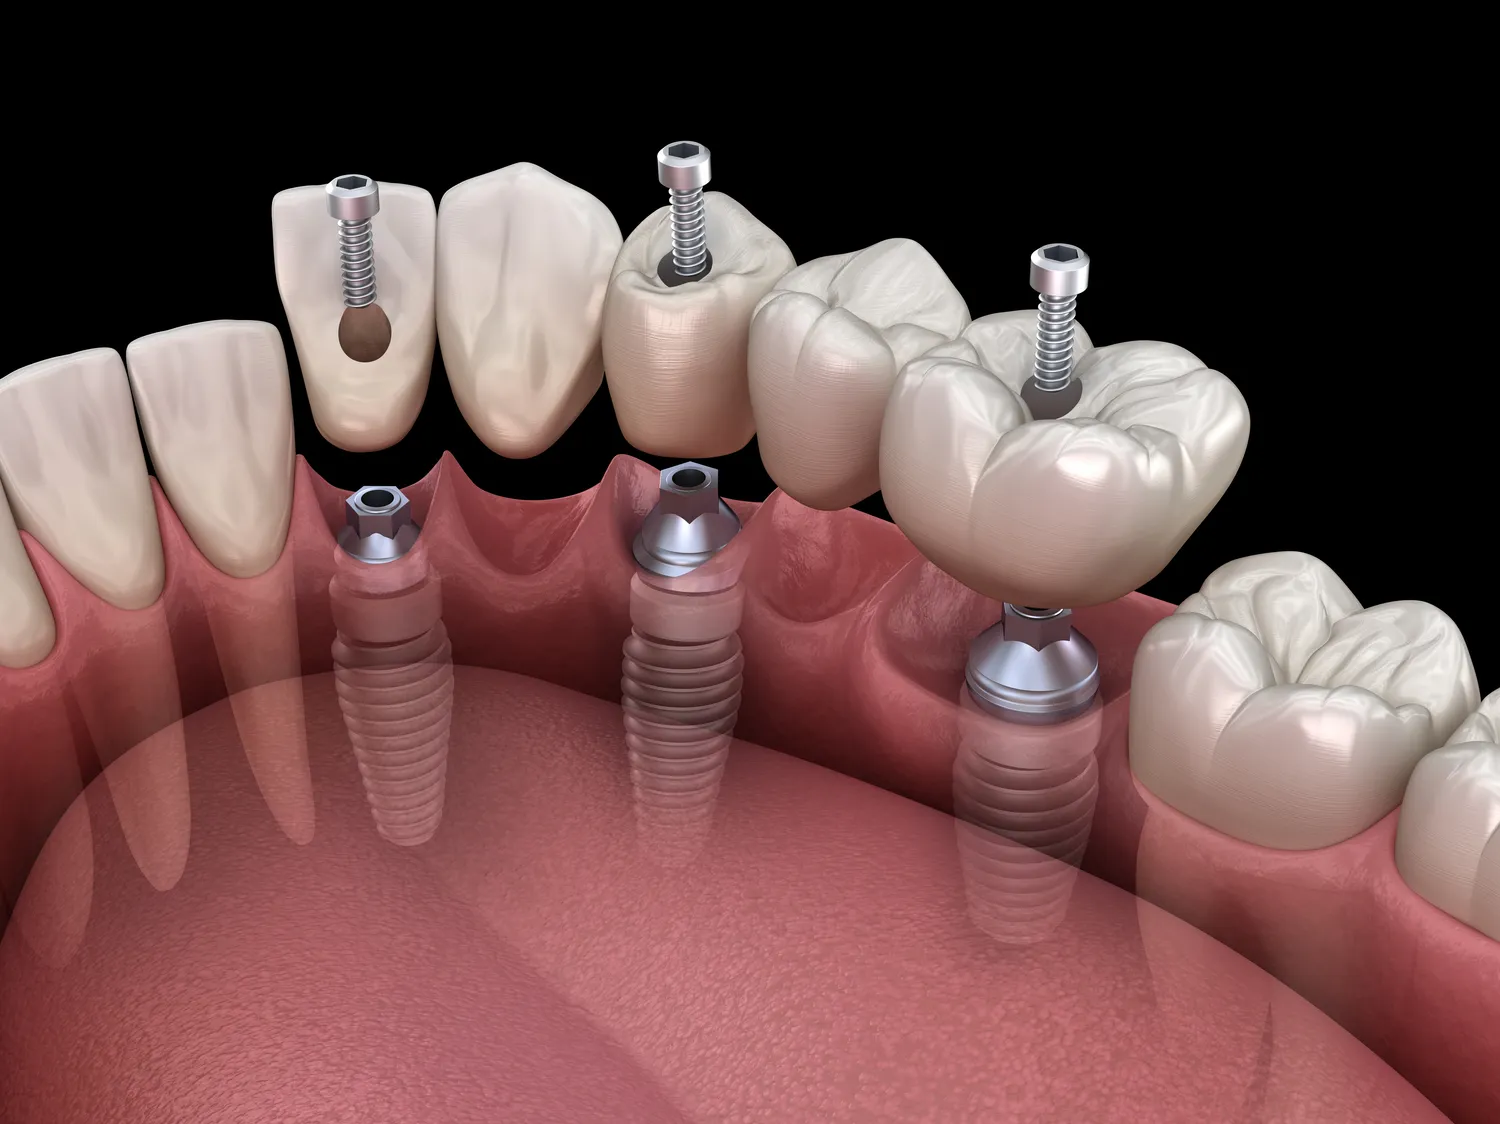

Proces Zęby w jeden dzień Szczecin rozpoczyna się od dokładnej diagnostyki oraz konsultacji stomatologicznej. Lekarz przeprowadza szczegółowe badania, aby ocenić stan jamy ustnej pacjenta oraz zaplanować odpowiednie kroki działania. Po wykonaniu niezbędnych zdjęć rentgenowskich i skanów 3D lekarz przystępuje do przygotowania planu leczenia. W zależności od potrzeb pacjenta może być konieczne usunięcie zębów, które są mocno uszkodzone lub chore. Następnie następuje etap wszczepienia implantów dentystycznych, które stanowią podstawę dla przyszłych protez. Po ich umiejscowieniu lekarz przystępuje do wykonania koron lub mostków protetycznych na miejscu, co pozwala na natychmiastowe zamocowanie nowych zębów. Cały proces trwa zazwyczaj kilka godzin i odbywa się w komfortowych warunkach kliniki stomatologicznej. Pacjenci mogą liczyć na znieczulenie miejscowe, co minimalizuje ból i dyskomfort związany z zabiegiem.

W zabiegu Zęby w jeden dzień Szczecin wykorzystuje się szereg nowoczesnych technologii, które znacząco poprawiają jakość i efektywność leczenia. Jedną z kluczowych innowacji jest skanowanie 3D, które pozwala na dokładne odwzorowanie struktury jamy ustnej pacjenta. Dzięki temu lekarze mogą precyzyjnie zaplanować każdy etap zabiegu, co minimalizuje ryzyko błędów i zwiększa komfort pacjenta. Kolejnym istotnym elementem jest drukowanie 3D, które umożliwia szybkie wytwarzanie indywidualnie dopasowanych koron oraz mostków protetycznych. To rozwiązanie nie tylko przyspiesza cały proces, ale także pozwala na uzyskanie znacznie lepszej estetyki i funkcjonalności zębów. Dodatkowo, wiele klinik korzysta z technologii cyfrowego projektowania uśmiechu, co daje pacjentom możliwość zobaczenia, jak będą wyglądać ich nowe zęby jeszcze przed przystąpieniem do zabiegu.